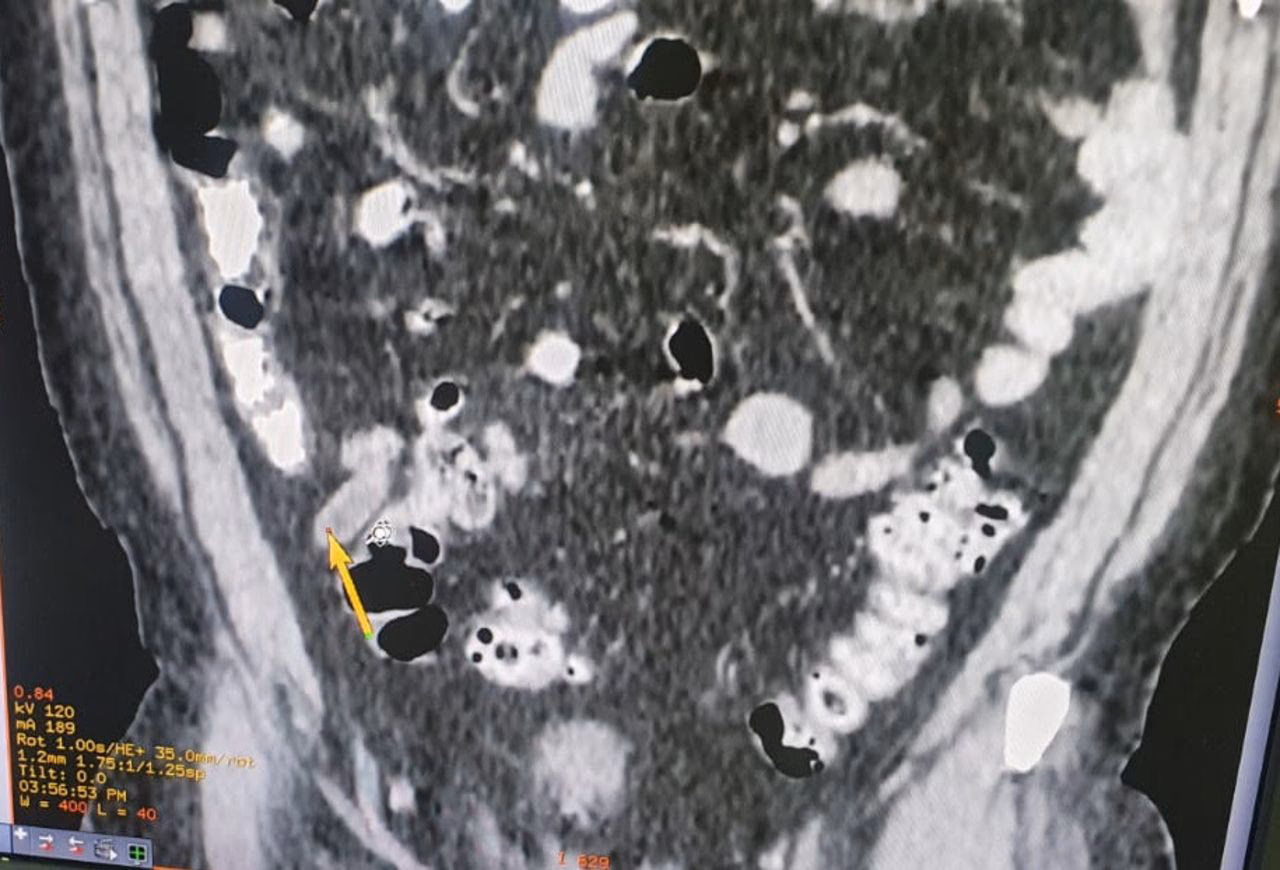

Trin 3: Røntgenbillede af brystkassen (thoraxrøntgen)

Hvis TST eller IGRA er positiv, eller hvis personen har symptomer på TB, vil det næste skridt næsten altid være et røntgenbillede af brystkassen. Dette gøres for at undersøge, om der er tegn på aktiv TB i lungerne, såsom forandringer i lungevævet.

- Røntgen af brystkassen: For at se efter tegn på TB i lungerne.